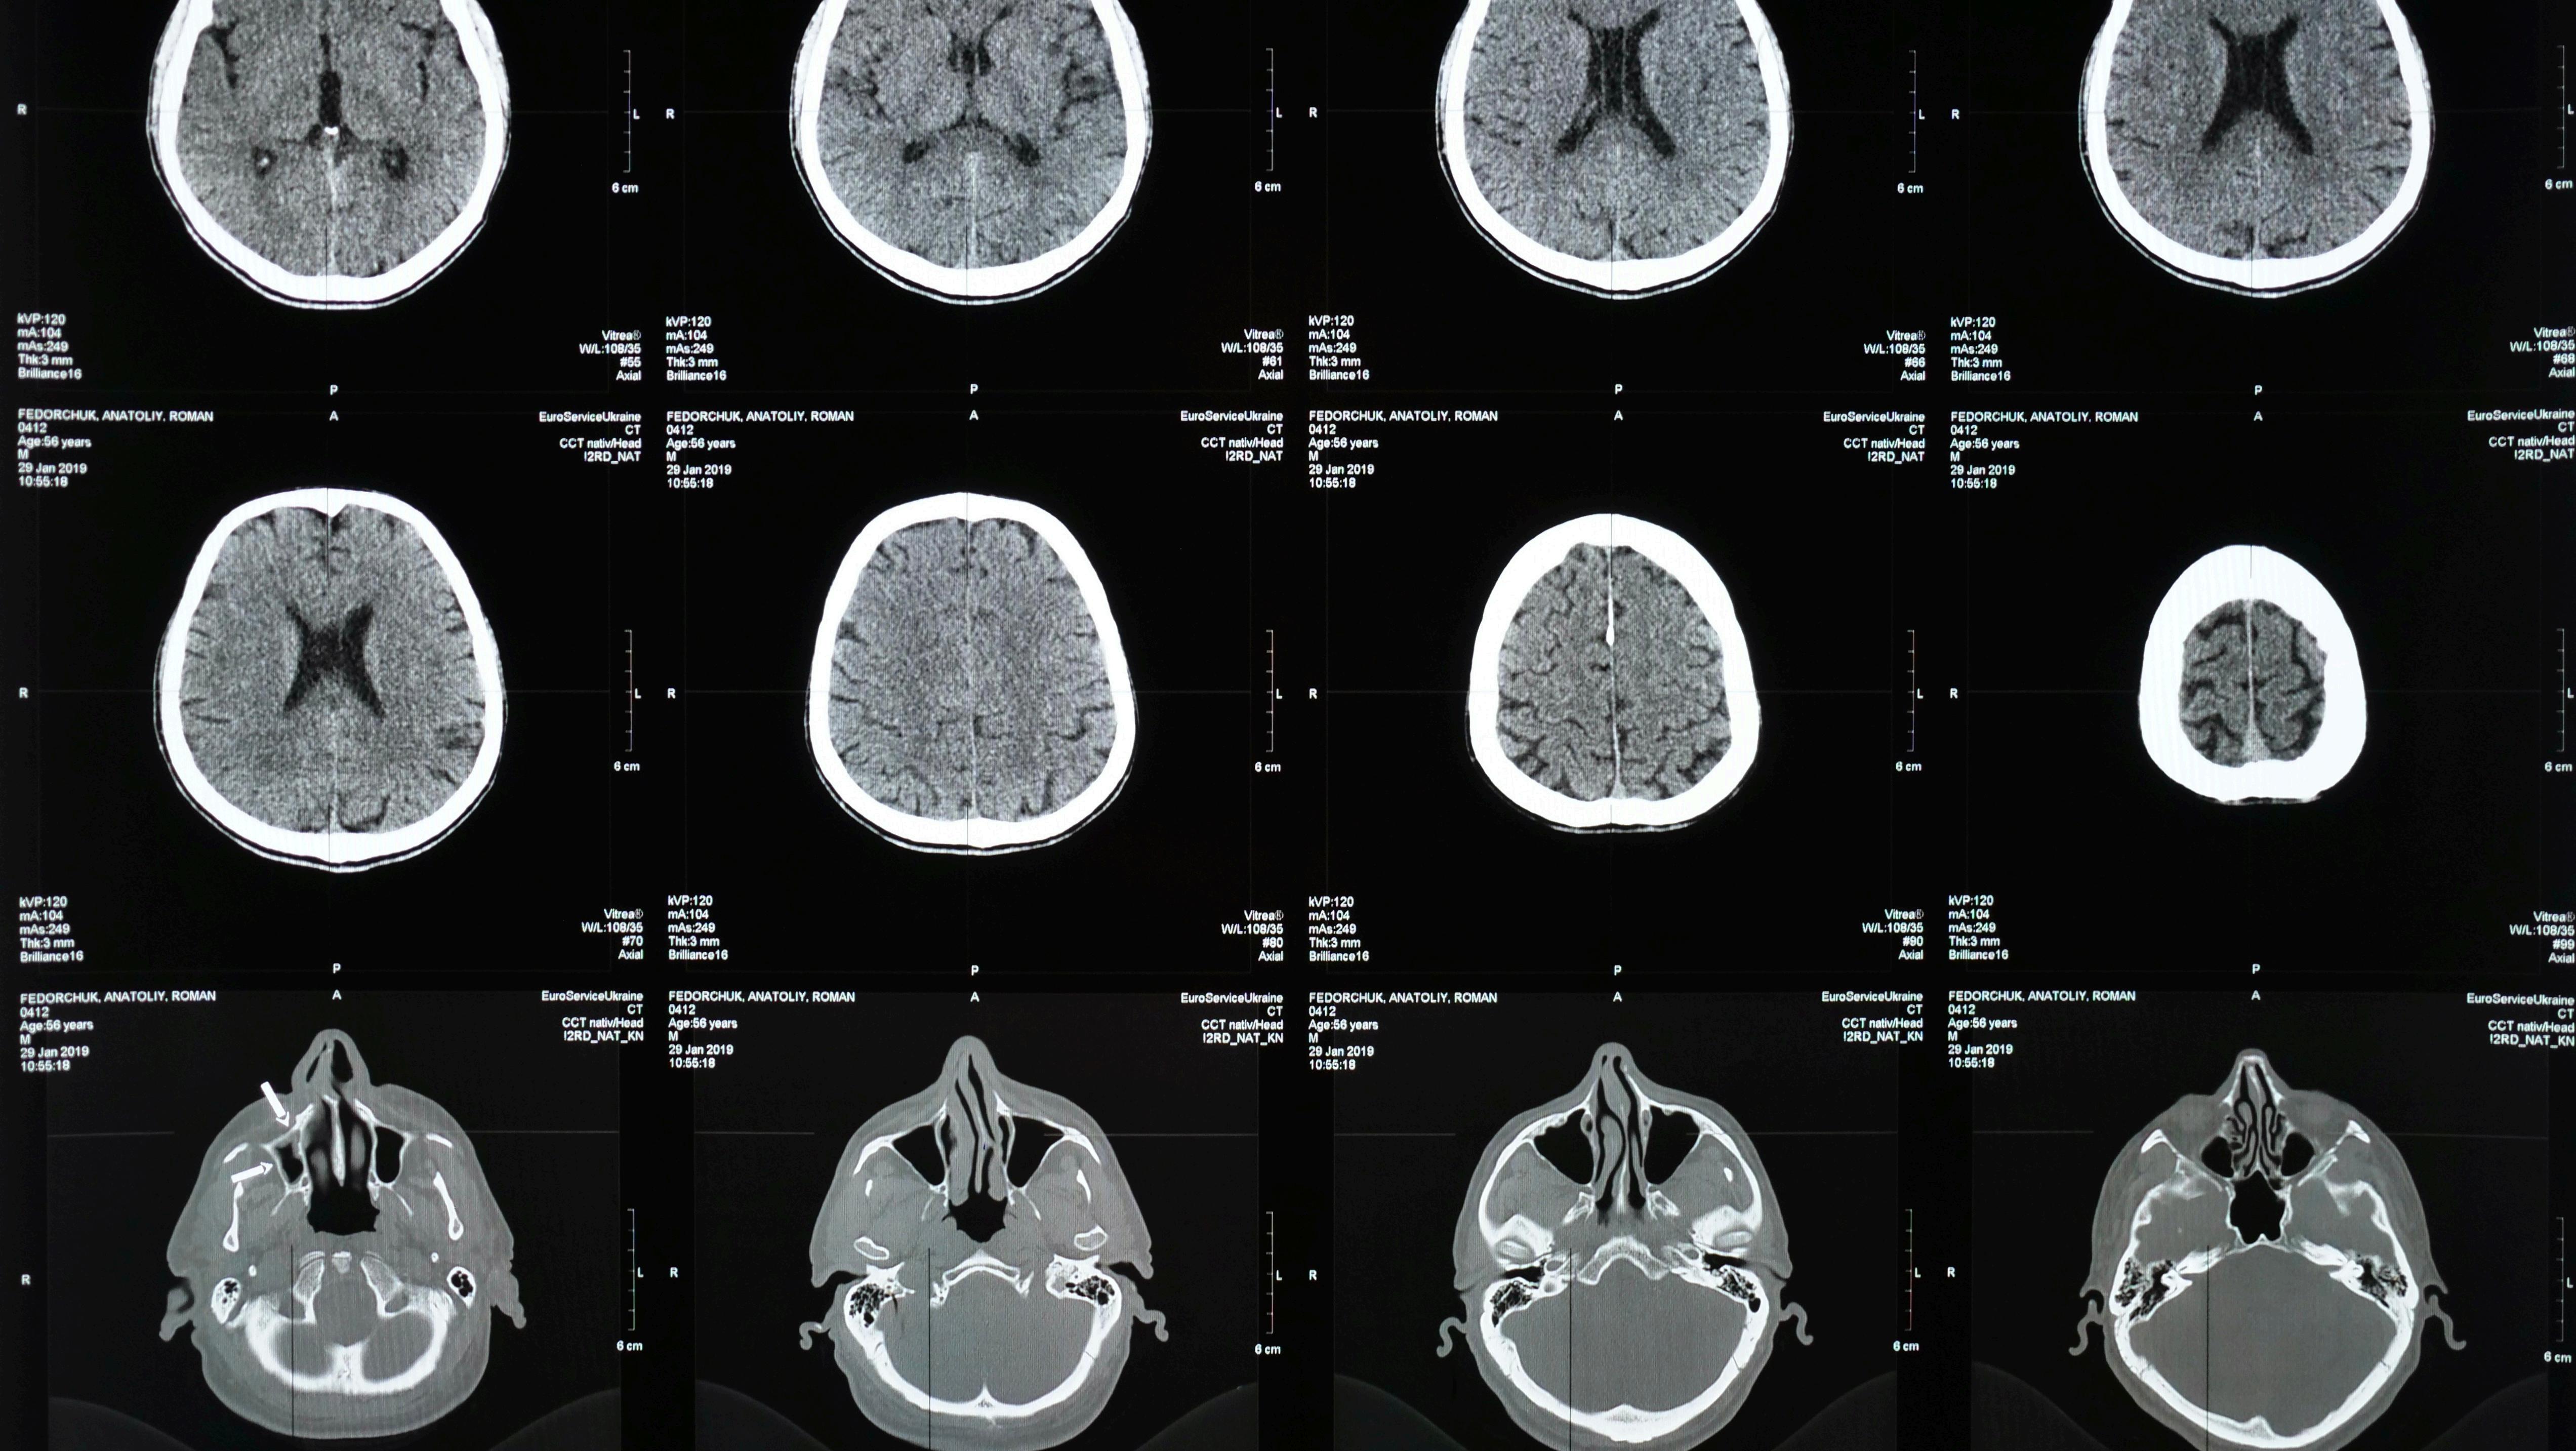

Neuralink and Dementia

Brain-computer interfaces (BCIs) came into development in the late 1960s and early 1970s. Over the decades, as technologyhasprogressed,humanityhas quickly reached the point where these devices that are generally seen as dangerous can now be implanted in a humanbraintobetestedandtrialled.BCIs come in many forms to aid people with debilitating conditions and disabilities to communicate, move, and perhaps even improvememory.Onesuchdeviceisthe ‘Link’producedbyNeuralink.

Currently,thedeviceisbeingtrialledontwo patientsthatarequadriplegic,tohelpthem moveandregaintheirautonomy.Eventually, itishopedthatpatientswithillnessessuch as dementia will be trialled and tested; however, there are concerns related to the invasive nature of the device. The general public are worried about what the companieswhoimplantthedevicesmaydo withthedata,aswellashowaccessibleand affordableitwillbe.

Neuralink is a piece of neurotechnology, specifically an implantable brain-computer interfaceintheformofachipthatwouldbe surgically implanted into the brain of a patient founded by Elon Musk in 2016. This technology aims to allow humans to communicatewithcomputers.Humantrials are currently ongoing with the first patient having received an implanted chip. As of August 2024, a second patient has successfully received the implant¹². The patient has been using computer-aided design (CAD) to design 3D objects, which theythen3D-print,suggestingtheimplantis working as intended, allowing patients to controldevicesastheywish.

By next year, Neuralink aims to have 11 patientsimplanted,andby2030,theaimis to have 22,000 patients receive implants⁶ . The goal of Neuralink is to enable patients with mobility problems and degenerative memory issues to regain their mobility and ability to retain information. This will be achieved by having the chip read the electrical impulses fired by the neurons, whichwillinturncreateareaction,suchas controlling prosthetics, devices, or software. Elon Musk believes it will revolutionise the treatmentofDementia,andpossiblycureit; however,thereareethicalconsiderationsand risksinvolvedwiththesurgeryitself,asitisan invasiveprocess.

There are many forms of dementia, with Alzheimer’sdiseasethoughttobethemost commonform.Manyofthediseasesthatfall undertheumbrellaofdementiaarecaused by an abnormal build-up of proteins in the brain¹⁰.Differenttypesofdementiacanalso be caused by damage to different areas of thebrain.Forexample,Alzheimer’sdiseaseis thought to be caused by high levels of the proteinbeta-amyloid,whichismadebythe breakdown of the larger protein amyloid precursor,bothinsideandoutsidebraincells, hinderingtheirabilitytocommunicate¹³.Itis thebraincellsinthehippocampusthatare responsibleforlearningandmemorythatare oftenthefirsttobedamaged².Thoughthere are treatments for the different types of dementia, due to it being caused by many diseases,suchasAlzheimer’s,frontotemporal dementia, dementia with Lewy Bodies etc, thereisnodefinitivecure³.

Musk’sBCI,named‘theLink’,chipusesthin, flexible threads that contain 1,024 electrodes⁵.Theseelectrodesarewhatrecord theneuralactivityoftheneuronsandnerve cells that send electrical signals across the body to control bodily functions. It is described as “cosmetically invisible”¹². The chip itself is around the size of a coin and worksbyrecordingtheelectricalsignalsand thendecodingthem.

After that, the decoded signals are transmitted back to the brain using electrical stimulation⁴. In essence, the chipsarecontrolledbytheusers’thoughts. The chip is surgically implanted into the cerebral cortex, which is the area of the brain responsible for memory, learning, andemotion.BCIscouldpossiblyenhance cognitivefunctionsthataredamageddue todementia;however,currentclinicaltrials with “the Link” have been focused on patients with motor neurone diseases. As humantrialsareonlybeginning,notmuch information has been released, and there hasyettobeanynewsfromNeuralinkon the use of the BCI in patients with degenerativecognitivediseases.Asaresult, itisonlyspeculationthatMusk’sBCIcould helptreatdementia¹⁴